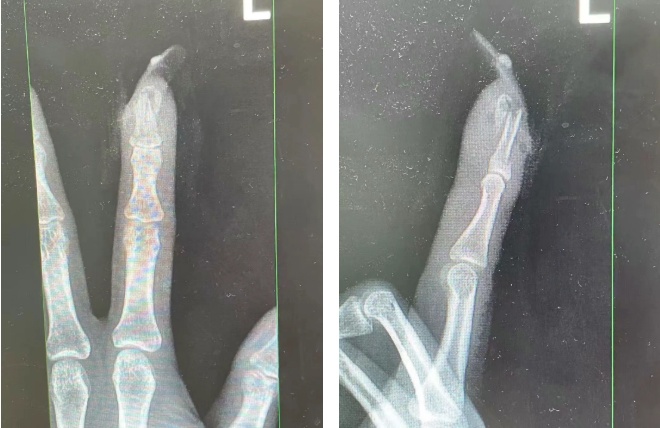

经检查

王女士指甲断裂,部分甲床外露

医生表示如果没有美甲

伤害不会这么严重

王女士受伤手指的X光影像。图源:杭州市临平区中西医结合医院